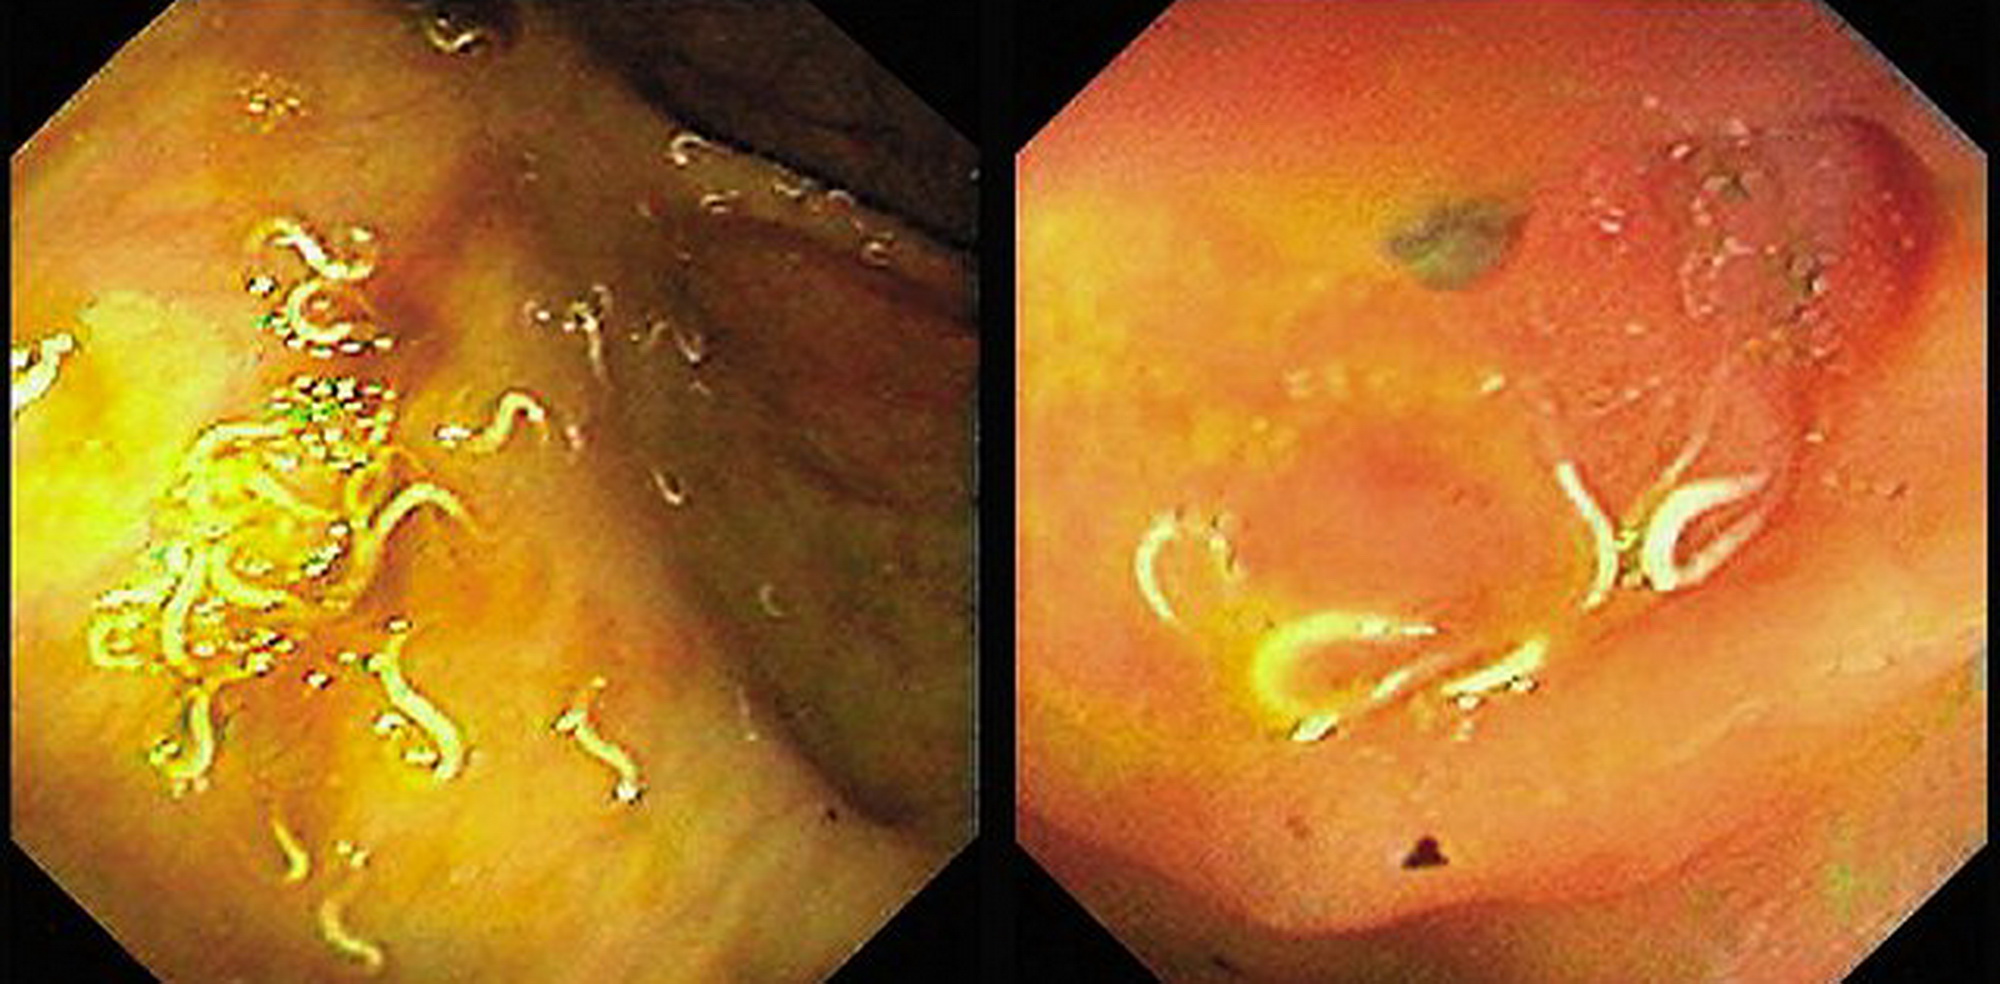

MEDICINA ONLINE OSSIURI VERMI INTESTINALI IMMAGINE (4)

Published 18/03/2019 at 2000 × 984 in Ossiuri (vermi intestinali): cause, trasmissione, come vederli, cura definitiva

MEDICINA ONLINE OSSIURI VERMI INTESTINALI IMMAGINE